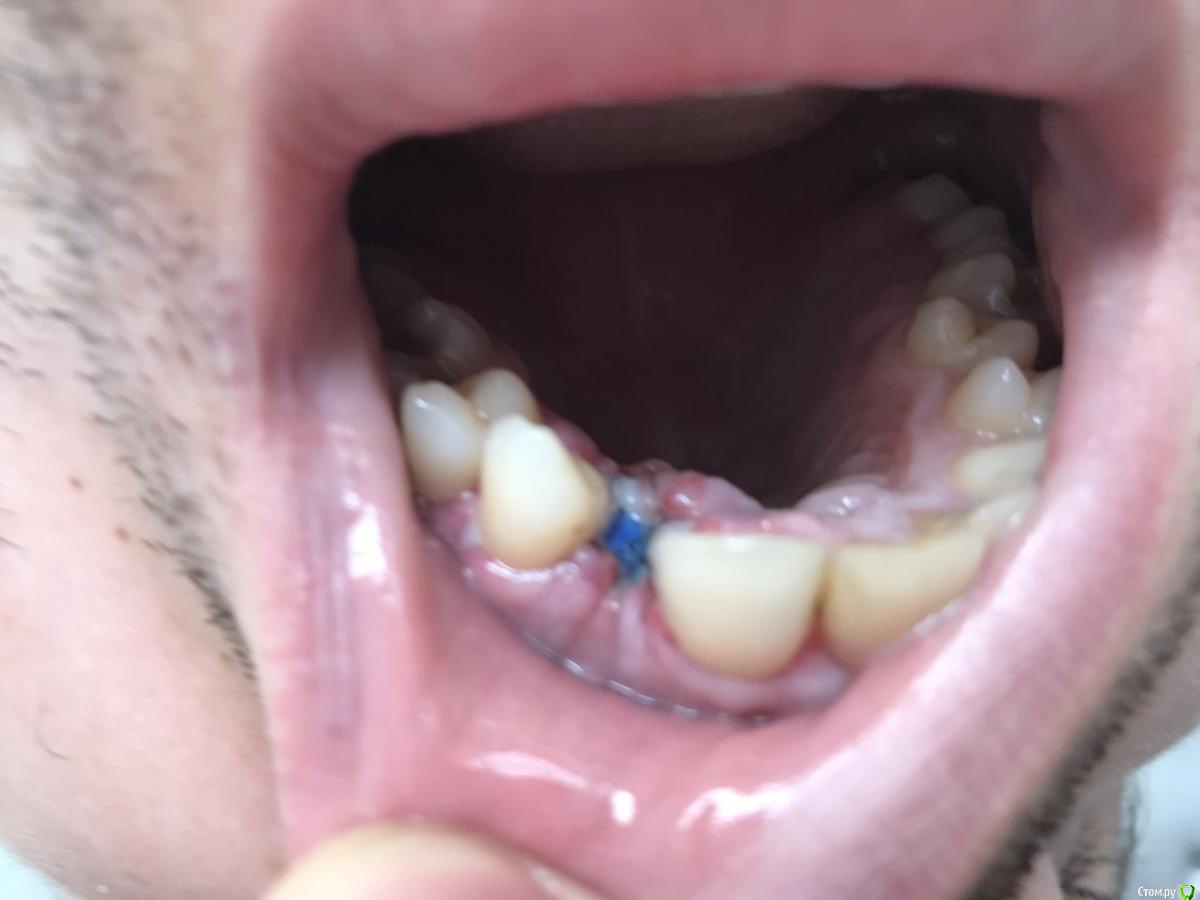

red_butler Опубликовано 21 марта, 2019 Поделиться Опубликовано 21 марта, 2019 Мне кажется или на фото между зубов мм 3, куда имплант ставить ??? 6 Ссылка на комментарий

dr.Dre Опубликовано 21 марта, 2019 Автор Поделиться Опубликовано 21 марта, 2019 (изменено) Мне кажется или на фото между зубов мм 3, куда имплант ставить ???верхняя челюсть планируется брекеты ,внизу уже установленные. Изменено 21 марта, 2019 пользователем dr.Dre Ссылка на комментарий